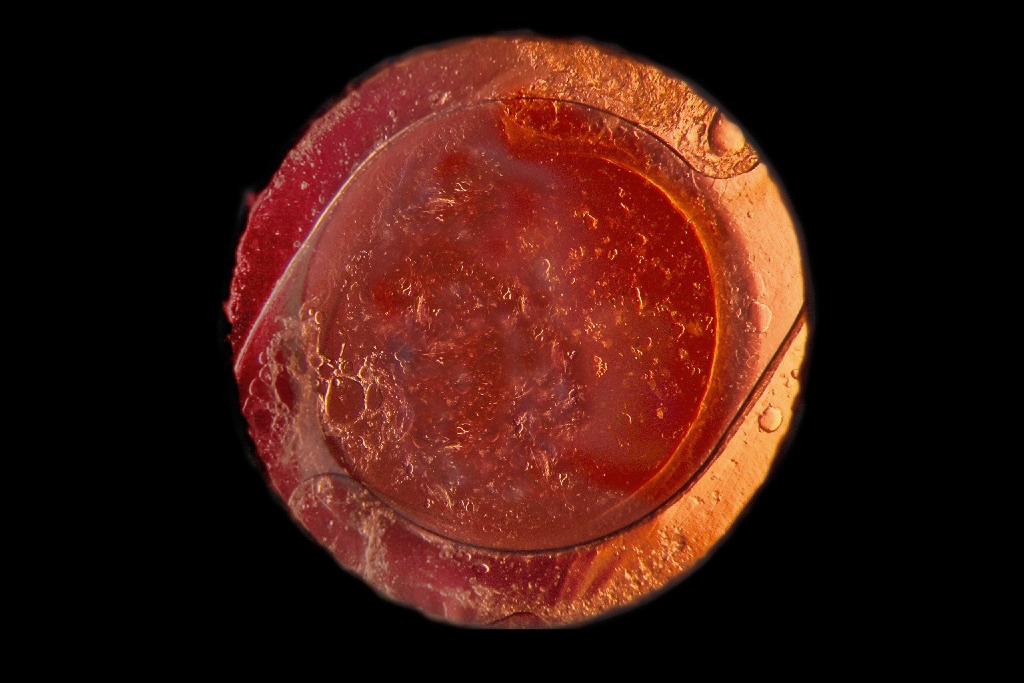

Brunescent cataract